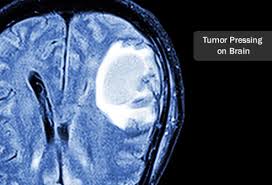

Malignant Brain Tumor Symptoms / Why A Brain Tumor Does Not Always Mean You Have Cancer Cleveland Clinic - There are more than 120 different kinds of brain tumors, depending onwhere they occur and what kinds of cells they are made of.. A brain tumor is an abnormal growth of tissue in the brain. There are an estimated 200,000 cases of brain tumors in the united states alone every year. These are the symptoms you should watch out for. A primary brain tumor starts with an abnormal brain cell and grows in the brain, and a metastatic tumor starts with an abnormal cell from another organ that makes its way into the brain, stays there, an. Does your head constantly hurt?

A primary brain tumor starts with an abnormal brain cell and grows in the brain, and a metastatic tumor starts with an abnormal cell from another organ that makes its way into the brain, stays there, an. It can happen to anyone at any age, but it's more common in people over age 40. However, they can also be a result of cancer that has spre. There are more than 120 different kinds of brain tumors, depending onwhere they occur and what kinds of cells they are made of. These tumors can be cancerous or noncancerous, and they can sometimes begin in the brain.

Due to interest in the. A brain tumor is an abnormal growth of tissue in the brain. Signs and symptoms of brain tumors in adults include severe headaches and seizures. Does your head constantly hurt? The tumor can either originate in the brain itself or come from another part of the body and travel to the brain.